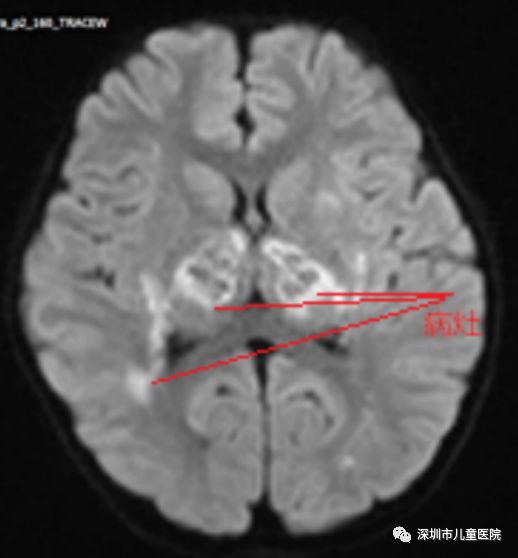

发烧第四天,核磁共振检查传来坏消息:她的脑部多发病灶,典型的急性坏死性脑病!PICU医生团队仔细分析后认为,这很可能是流感引起的脑病。进一步的检验后,“祸首”被揪了出来——甲型流感

通过检查发现这孩子的头颅CT是一个明显的多发病灶,我们考虑孩子是一个甲流病毒引起的急性坏死性脑病。急性坏死性脑病是儿童在甲流里经常会碰到的并发症,孩子很快会出现意识障碍,严重的甚至会出现脑损伤。